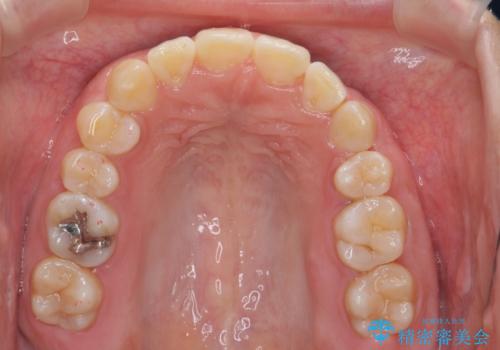

よくある悩み 前歯が裏に2本入っているのを治したい

最小限の抜歯により矯正ができたと、喜んでいただきました。